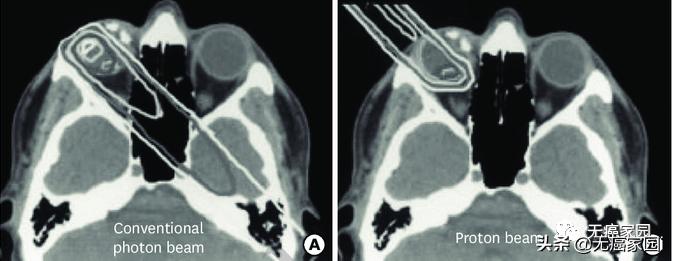

左图为常规光子束治疗,右图为质子束治疗

研究结果显示,与传统的光子放射疗法(EBRT)相比,PBRT具有物理优势。在下图的典型病例示意图中, 传统光子治疗在眼内靠近肿瘤的部位剂量较大,而且后眼眶和脑内肿瘤远端的剂量也明显高于质子治疗。

研究表明,在维持眼球的情况下,质子束具有比常规光子束更低的辐射剂量,而且最终可以使眼功能最大化。